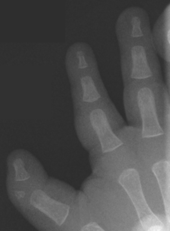

Triphalangeal thumb

First described by Columbi in 1559,[1] triphalangeal thumb (TPT) is a congenital malformation where the thumb has three phalanges instead of two. The extra phalangeal bone can vary in size from that of a small pebble to a size comparable to the phalanges in non-thumb digits. The true incidence of the condition is unknown, but is estimated at 1:25,000 live births.[2] In about two-thirds of the patients with triphalangeal thumbs, there is a hereditary component.[3] Besides the three phalanges, there can also be other malformations.

The triphalangeal thumb has a different appearance than normal thumbs. The appearance can differ widely; the thumb can be a longer thumb, it can be deviated in the radio-ulnar plane (clinodactyly), thumb strength can be diminished. In the case of a five fingered-hand it has a finger-like appearance, with the position in the plane of the four fingers, thenar muscle deficiency, and additional length. There is often a combination with radial polydactyly.